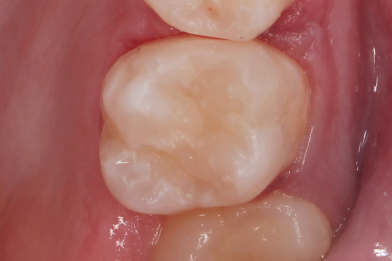

Лечение среднего кариеса 2.6. Функциональная и эстетическая реставрация зуба

Эвинян Лусине Артоевна -